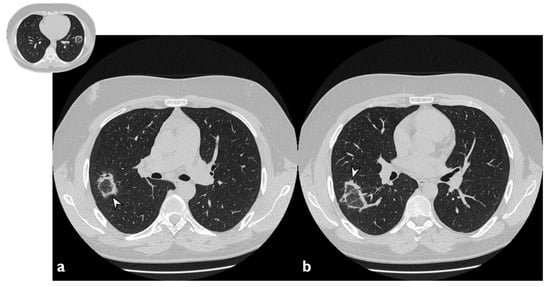

3.4. Nodular Pattern

A complete resolution after therapy was observed in three of the five cases with nodular pattern (Figure 11), whereas two subjects have shown a partial reduction in number and size. Only one patient did not report nodule resolution after treatment. In one patient—who did not show nodules or masses at the first CT—we have observed the presence of new nodular lesions despite therapy (Figure 12) (Table 7).

Figure 11. On the left (a): baseline HRCT; peripheral solid nodule in the right lower lobe (arrowheads). On the right (b): HRCT after oral corticosteroid (OCS) therapy; the previous nodule is no longer present.